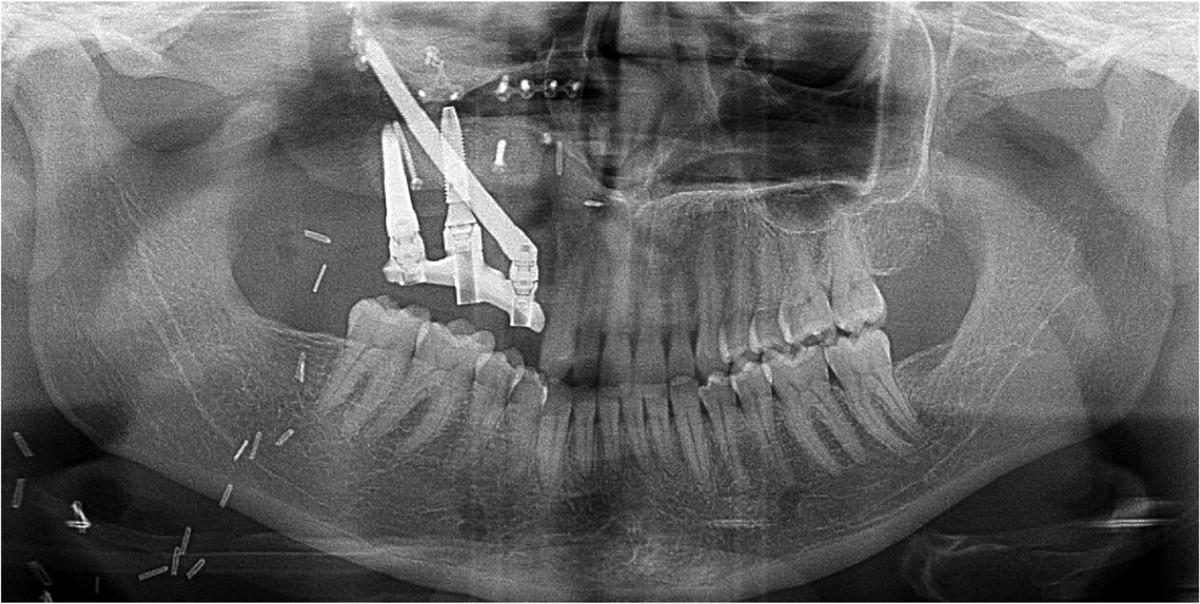

Panoramic radiograph showing the placement of 2 ZI (position 14 and 17) and 1 intercalary CI (position 15).